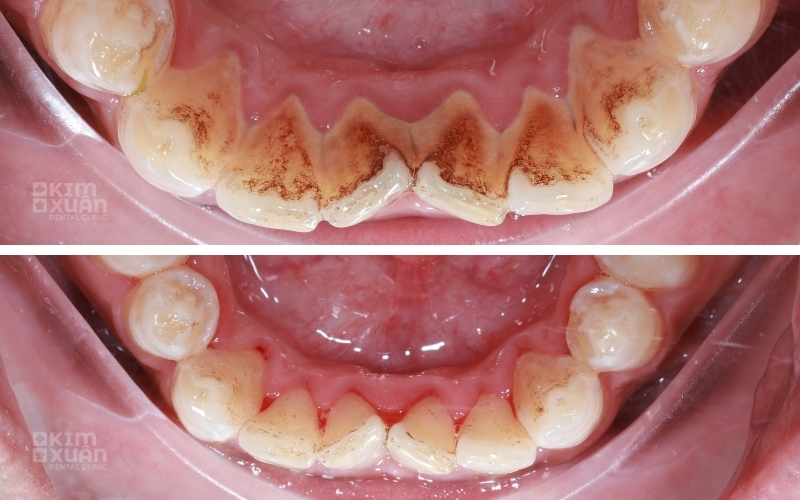

Xuất hiện mảng vôi màu vàng hoặc nâu bám quanh viền nướu

Nguyên nhân là do quá trình cạo vôi răng giúp loại bỏ lớp mảng bám vàng nâu, cao răng cứng và các vết ố tích tụ lâu ngày trên bề mặt răng. Nhờ đó, răng sẽ trở lại màu men tự nhiên và trông trắng sáng hơn trước.